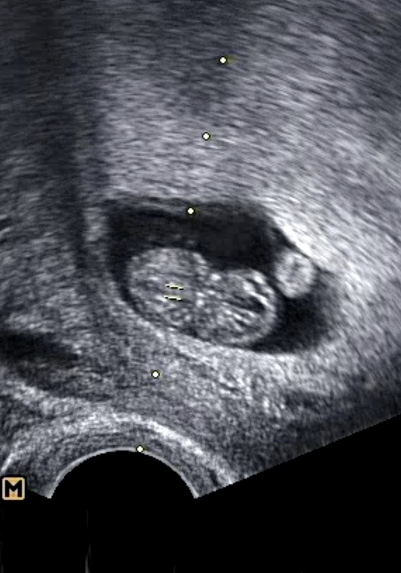

점점 커갈때마다 임산부는 힘들어하고 아기도 걱정되고 심하게 배가 땡기고 아플때마다 병원을 방문했습니다. 조금씩 출혈이 초음파에서 잡히기도 했고 의사선생님께서는 계속 눕거나 안정을 취해야 한다고만 하셨습니다. 토를 안하려고 신맛이 나는 사탕,젤리를 자주 먹었지만 갑자기 나오는 토는 참을수가 없습니다. 밖에 나갈때는 비닐이 필수였습니다.